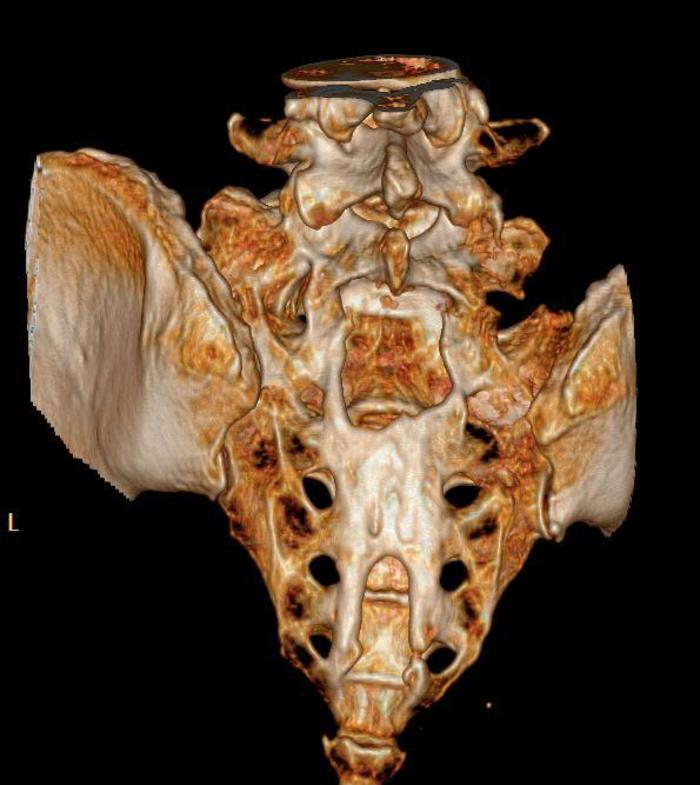

中年女性,骶管小囊肿,当地医院2年前手术,术后症状加重,骶尾臀部剧烈疼痛,VAS 7分,不能站、立、行超过15分钟,术后至今每天服用止痛药。从影像来看,骶管囊肿并不大,为何术后疼痛这么明显呢?应该怎么处理呢

术中:1. 骶管囊肿虽然很小,但漏口很大;予以严密的封堵;2. 由于初次手术未修补骶骨骨窗,所以患者不能久站,本次手术用钛板修复骨窗,重建一个骨性的压力屏障。